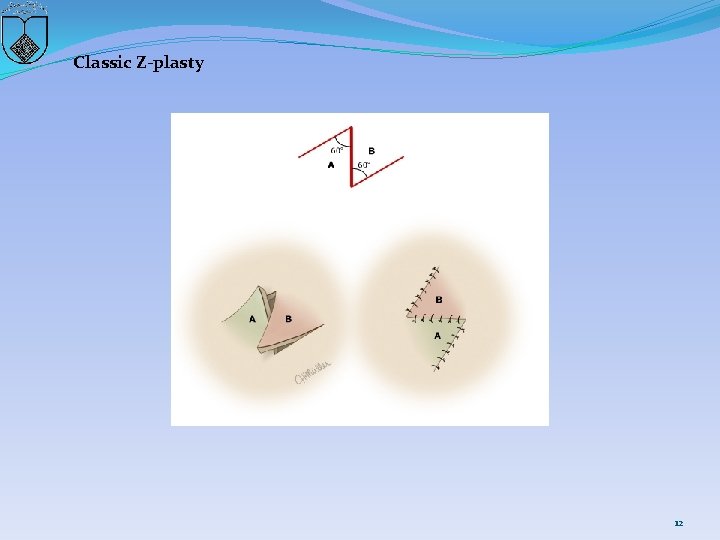

Ultrasonographic or magnetic resonance imaging � helps to define the location and thickness of the septum and to differentiate between a high septum and congenital absence of the cervix � A septum : excise and repair � Reanastomosis is easier if the upper vagina has been distended with menstrual blood products, as this acts as a natural tissue expander to increase the amount of upper vaginal tissue available for the reanastomosis. � preoperative use of vaginal dilators may thin the septum and facilitate reanastomosis. � A Z-plasty technique � Approximately 36 pregnancies have been reported in women with transverse septa. One-half had planned cesarean delivery, most of the rest had incision or instrumental dilation during labor, and a few underwent incision before pregnancy. Outcomes were generally good. 10